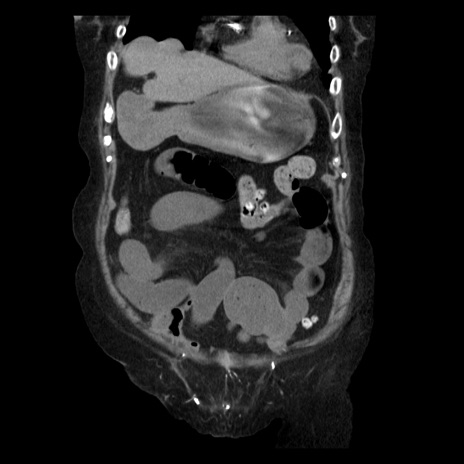

症例14(冠状断像)

【症例】 90歳代女性

【主訴】 腹痛・嘔吐

【現病歴】今朝から左側腹部痛を認めた。 経過観察していたが、嘔吐を認めたため来院。

【既往歴】 子宮癌術後

【身体所見】 意識清明、BP 127/54mmHg、P 98bpm Sp02 95%(RA)、BT 35.8°C、腹部平坦・軟腸ぜん動音聴取良好、右下腹部圧痛(+) 反跳痛なし

【データ】WBC 9800、CRP 0.46